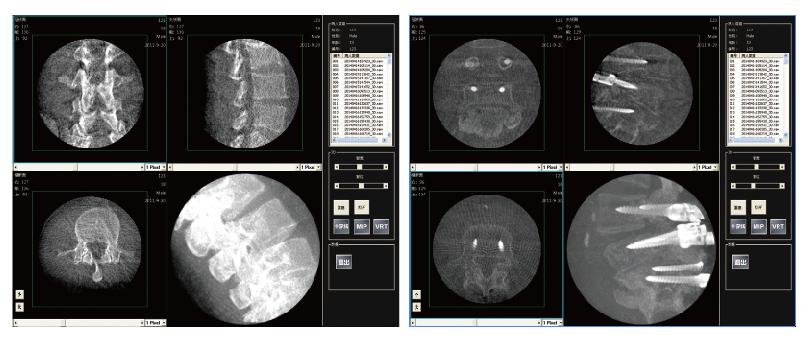

PLX7200三维C形臂骨科手术应用

1、有利于使用者在三个面上检测手术进程。

2、植入物位置更加准确,确保手术安全,提高手术的效果。

3、通过一次多角度自动采集,既可获得全面、准确的影像信息,减少重复采strdfgwgl集次数,投照剂量和手术时间也相应减少。

4、在手术结束之前使用,在手术室既可以完成三维评估,准确地检测定位误差并及时进行修正,不再需要术后移至CT室进行复查,减少因错位等原因进行二次手术的可能。